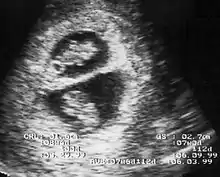

By performing an obstetric ultrasound at a gestational age of 10–14 weeks, monochorionic-diamniotic twins are discerned from dichorionic twins. The presence of a "T-sign" at the inter-twin membrane-placental junction is indicative of monochorionic-diamniotic twins (that is, the junction between the inter-twin membrane and the external rim forms a right angle), whereas dichorionic twins present with a "lambda (λ) sign" (that is, the chorion forms a wedge-shaped protrusion into the inter-twin space, creating a rather curved junction).[4] The "lambda sign" is also called the "twin peak sign". At ultrasound at a gestational age of 16–20 weeks, the "lambda sign" is indicative of dichorionicity but its absence does not exclude it.[5]

In contrast, the placentas may be overlapping for dichorionic twins, making it hard to distinguish them, making it difficult to discern mono- or dichorionic twins on solely the appearance of the placentas on ultrasound.